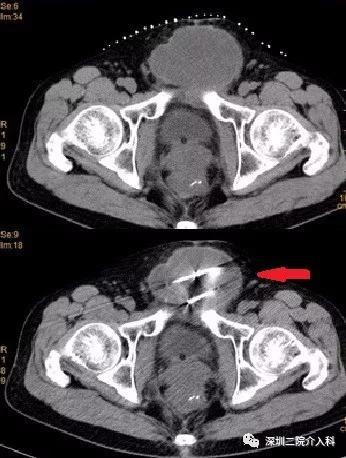

图示CT引导下,经过精密计算肿瘤大小及消融范围后,分别置入4根冷刀: